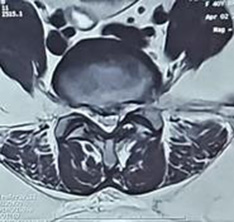

Fig. 3. Axial T2-weighted MRI showing the central disc prolapse with right-sided protusion compressing the nerve roots